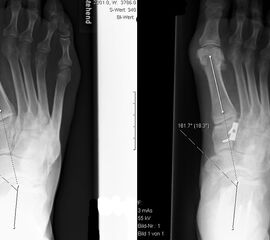

Lateralisierende Calcaneus-Osteotomie (Abb. 2 und 3, Video 2)

Die lateralisierende Calcaneus-Osteotomie ist ein Standard-Operationsschritt bei fast jeder Hohlfuβkorrektur. Der biomechanische Effekt der Osteotomie ist eine Verschiebung des Fersenkontaktpunktes und damit der beim Rückfuβ varus medialisierten Belastungsachse durch das OSG nach lateral. Diese statische Rückfuβ-Korrektur allein ist in der Lage, den bei Pes cavovarus anteromedial erhöhten OSG-Druck, der sehr wahrscheinlich zur korrespondierenden Arthrose führt, zu neutralisieren 7. Zuklappende Osteotomien mit Entnahme eines lateralen Knochenkeils haben sich dabei weniger effektiv gezeigt als solche mit Lateralisation des Tubers. Mit der Lateralisation des Achilles-Ansatzes verringert sich die Inversionskraft der Sehne zugunsten der schwachen Eversion, wodurch gleichzeitig die Prädisposition für Supinationstraumata reduziert wird. Neben der klassischen Dwyer-Osteotomie (Entnahme eines lateralen, vertikalen Keils 8 haben sich vor allem die technisch einfache Verschiebe-Osteotomien („sliding osteotomy“) und die Z-förmigen Osteotomien (Pisani 1993, Malerba 9) mit Entnahme eines lateralen Keils aus dem horizontalen Anteil der Osteotomie aber ohne Lateralisation des Tuberfragmentes, sowie die Korrektur nach Hintermann (Knupp 2008) mit zusätzlicher Lateralisation des Tuberfragmentes) durchgesetzt. Bei neutral aligniertem OSG ist keine supramalleoläre Tibia-Osteotomie zur Korrektur des Rückfuβ varus indiziert. Generell sollten Osteotomien gegenüber korrigierenden Arthrodesen der Vorzug gegeben werden. Die im Folgenden beschriebene Verschiebeosteotomie ist technisch einfach und hinsichtlich OSG-Druckneutralisation ebenso effektiv wie die Z-Osteotomien 7.

• Umfahren des Calcaneus mit Hohmann Hebeln und Markieren der Osteotomie mit 2 1.6 Kirschnerdrähten; Kontrolle der korrekten Osteotomie-Ebene im BV, diese sollten, da in der Regel keine Verkürzung oder Verlängerung des Rückfuβes gewünscht ist, in der axialen Projektion genau rechtwinklig zur Achse des Calcaneus verlaufen; seitlich beginnt die Osteotomie proximal etwa 2 cm anterior des Achilles-Ansatzes und läuft etwas schräg nach distal-anterior.

• Kontrolle der korrekten Schraubenlage im BV (Abb. 3).